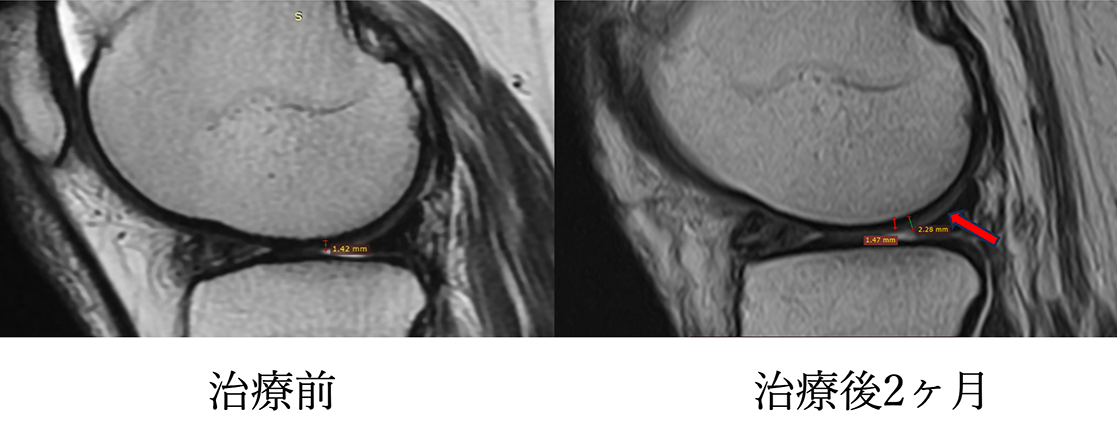

MRI画像でも炎症は治まり、半月板の再生や軟骨が生えてきていることを確認。

半月板の炎症や腫大軽快。

膝周囲の炎症(白っぽさ)が軽快している